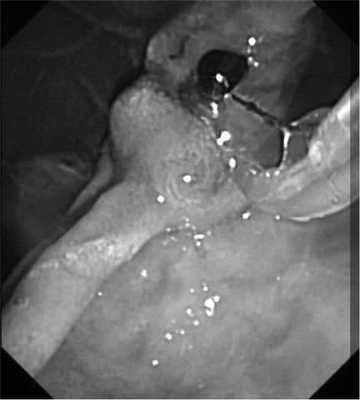

При поступлении состояние больной относительно удовлетворительное. Индекс массы тела 23 кг/м 2 . Кожные покровы бледные, доступные для пальпации лимфатические узлы не увеличены. Температура тела 36,8 °С. Дыхание везикулярное, проводится во все отделы грудной клетки, хрипов нет. Частота дыхательных движений 19 в минуту. Тоны сердца ритмичные, приглушеннные. Артериальное давление 125/80 мм рт.ст., пульс 72 удара в минуту. Язык влажный. Живот не вздут, мягкий, участвует в акте дыхания. При пальпации болезненный в эпигастральной области, симптомов раздражения брюшины нет. Перистальтика кишечника активная, равномерная. Печень не увеличена, селезенка и желчный пузырь не пальпируются. Симптом Пастернацкого отрицателен с обеих сторон. Мочеиспускание свободное, безболезненное. Стул оформленный, в течение двух дней перед поступлением темного цвета. При ректальном исследовании патологических новообразований прямой кишки не выявлено, сфинктер тоничен, ампула прямой кишки пустая, со следами кала черного цвета. В общем анализе крови отмечено снижение уровня гемоглобина до 92 г/л и уровня эритроцитов до 3,8·10 12 /л. Другие показатели лабораторных анализов (общего анализа мочи, биохимического анализа крови, коагулограммы) в пределах нормы. Помимо лабораторных анализов, в экстренном порядке выполнены электрокардиограмма (ЭКГ), ЭГДС и ультразвуковое исследование органов брюшной полости и малого таза, пациентка осмотрена гинекологом, терапевтом. ЭКГ: синусовый ритм, горизонтальное положение электрической оси сердца, признаки нагрузки на правое предсердие, изменения миокарда левого желудочка. УЗИ органов брюшной полости и малого таза: объемное полостное образование в области 12ПК, размером 7×5 см, сообщающееся с просветом 12ПК. Заключение: дивертикул 12ПК? При ЭГДС картина хронического гастрита, дуодено-гастрального рефлюкса. В 12ПК на границе ее перехода верхнегоризонтальной части в вертикальную, по переднебоковой стенке выявлен большой дивертикул, размером 7×4,5 см с признаками состоявшегося из него кровотечения. Полость дивертикула отмыта от пищевых масс и сгустков крови, продолжающегося кровотечения нет, однако полностью осмотреть стенки дивертикула не представилось возможным из-за его деформации и риска перфорации. Заключение: крупный дивертикул 12ПК, осложненный состоявшимся кровотечением (рис. 1). Рис. 1. Эндофото при выполнении ЭГДС, просвет двенадцатиперстной кишки и устье дивертикула (справа) после отмывания. При осмотре гинекологом выявлена миома матки малых размеров. В связи с отсутствием продолжающегося желудочно-кишечного кровотечения и стабильным состоянием больная госпитализирована в отделение хирургии для дообследования и определения тактики лечения. На рентгенограмме органов грудной клетки (27.11.18) патологии не выявлено. Рентгеноскопия желудка и 12ПК с пассажем бария (28.11.18): на границе перехода верхнегоризонтальной части в вертикальную определяется крупный дивертикул размером 7×5 см, эвакуация контраста из желудка своевременная, проходимость по 12ПК не нарушена (рис. 2). Рис. 2. Отсроченная рентгенограмма желудка и двенадцатиперстной кишки после пассажа бария, контрастированный дивертикул двенадцатиперстной кишки.